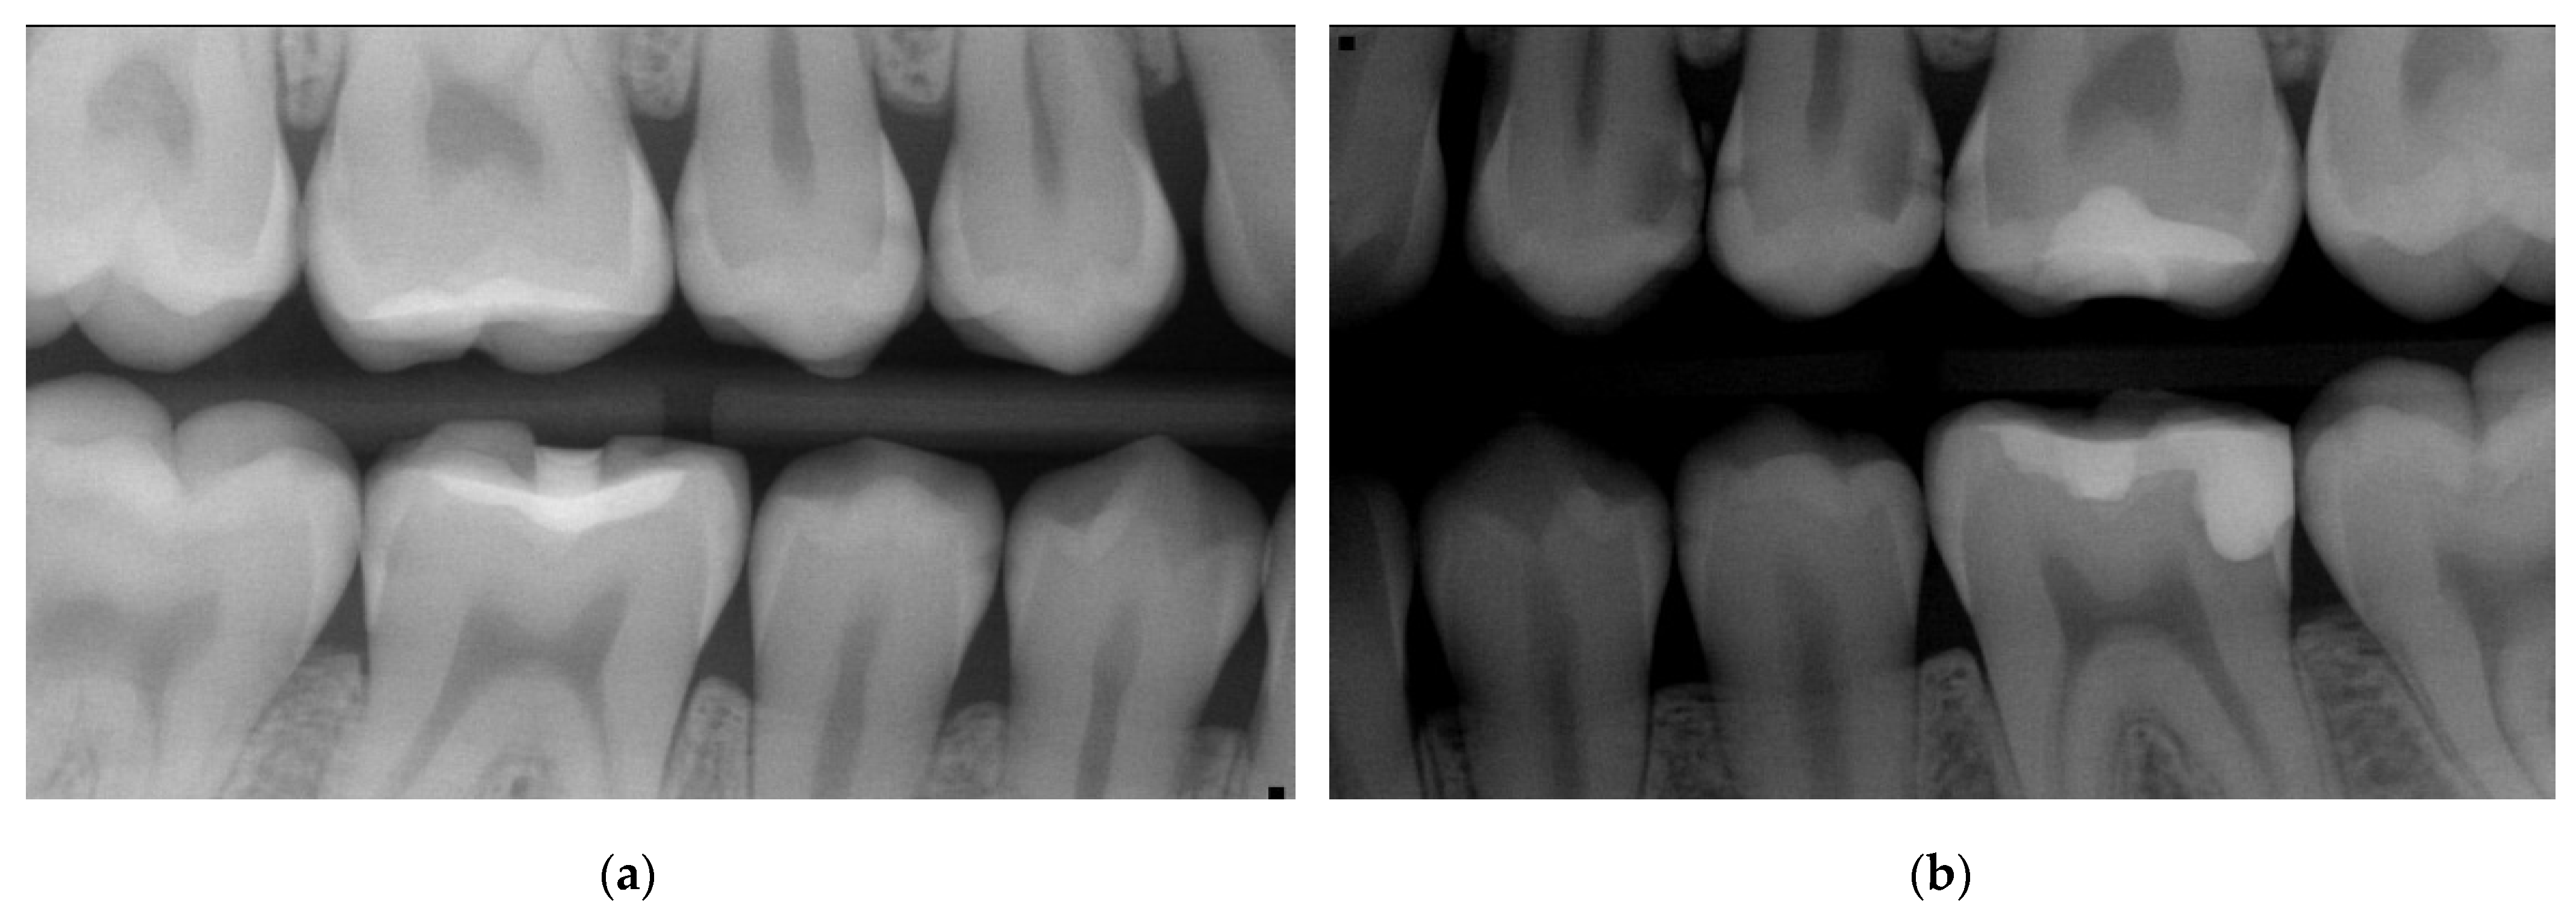

- Bitewings radiographs: During the same dental visit, bitewing X-rays were taken to confirm the presence of lesions and to determine their depth and proximity to the pulp (Figure 1). The ADA proximal caries classification system was used to diagnose and monitor progression of these lesions: E1: lesion in the outer half of the enamel; E2: lesion within the inner half of the enamel; D1: lesion passing the enamel dentin junction (EDJ) and within the outer third of dentin; D2: lesion within the 2nd third of the dentine; D3: deep lesion passing the 2nd third of the dentin [16]. For evaluations of the bitewing X-rays, three calibrated pediatric dentists classified the lesions independently in a dark room with the option to digitally modify the contrast and brightness of the X-rays. In the rare cases of disagreement, consent was reached via a discussion (Table 1). Bitewings were taken using a Sirona Heliodent DS and a Xios XG supreme intraoral sensor, with a standard dose of 0.16 mAs. The same criteria for bitewings were considered also for the follow-up visit which was at the same time the pre-SDF radiographic examination (Figure 2).

| Figure 1—11/2019 | ? | 0 | E1 | E2 | E2 | E2 | D1 | 0 | D1 | E2 | D1 | D2 | 0 | 0 |

| Figure 2—02/2022 | ? | D1 | D1 | D1 | E2 | D1 | - | - | D2 | D1 | D1 | D3 | E2 | ? |

| Figure 6—07/2023 | ? | D1 | D1 | D1 | E2 | D1 | F | 0 | F | F | D1 | F | E2 | 0 |

| Tooth | 47 | 46 | 45 | 44 | 34 | 35 | 36 | 37 | ||||||

| Surface | M | D | M | D | M | D | D | M | D | M | D | M | ||

| Figure 1—11/2019 | 0 | 0 | E1 | E1 | 0 | 0 | E2 | E1 | E2 | 0 | 0 | ? | ||

| Figure 2—02/2022 | 0 | 0 | E1 | E2 | 0 | 0 | E2 | E1 | E2 | E1 | E1 | ? | ||

| Figure 6—07/2023 | 0 | 0 | E1 | E2 | 0 | 0 | E2 | E1 | E2 | E1 | ? | 0 | ||